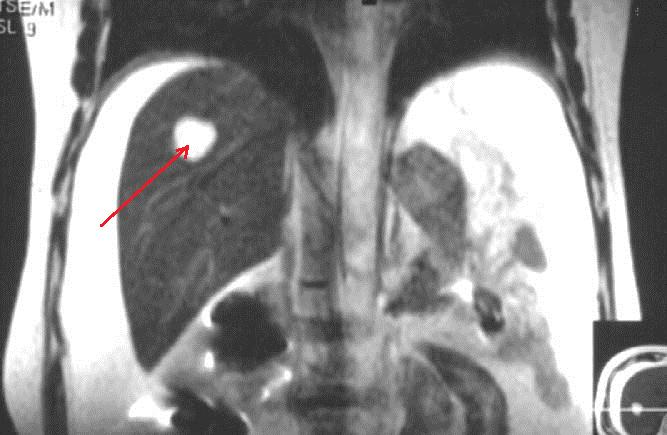

肝内结节,为海绵状血管瘤

弄清楚了吗?总结一下吧!